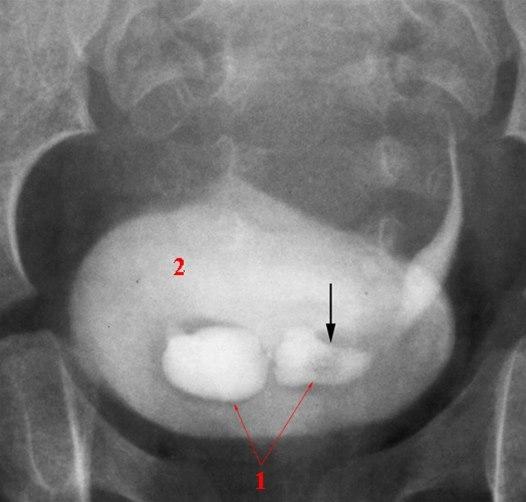

Bilaterale kontrastfylte ureteroceler (1)

Det venstre ureterocelet har en sentral kontrastdefekt forenlig med et lite konkrement (pil)

Urinblæra (2).